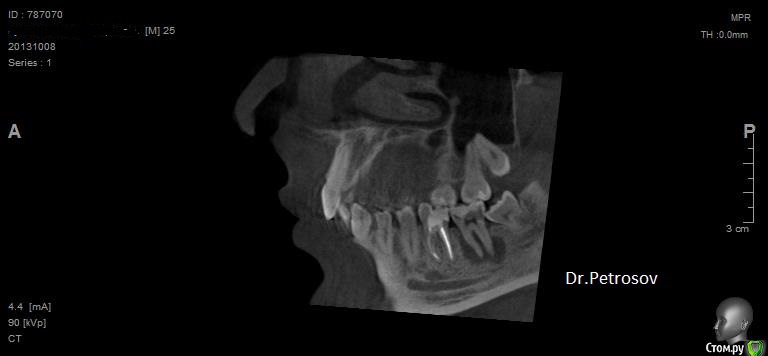

Dr.Feliks Опубликовано 16 февраля, 2015 Автор Поделиться Опубликовано 16 февраля, 2015 (изменено) Еще один интересный случай. Но перед тем, как описать его - снимок. Из клиники - жалобы на периодические ноющие боли в зубе. Объективно - зуб восстановлен пломбой на 2/3 площади коронки (девитальный, эндодонтия очень давно проводилась), в медиальных и дистальных поверхностях ниже уровня десневого края. Стенки тонкие, эмаль мягкая, хрупкая.Вопрос - стоит ли браться и как поступили бы Вы?Еще вопрос, коллеги, почему не могу создать еще темы для обсуждения? Приходится в этой теме размещать другой случай? Изменено 16 февраля, 2015 пользователем Dr.Feliks Ссылка на комментарий

Dr.Feliks Опубликовано 16 февраля, 2015 Автор Поделиться Опубликовано 16 февраля, 2015 Насколько ниже уровня десны? Возможно ли технически удлинить коронку?на 1-1.5 мм относительно маргинального края. технически восстановить зуб не проблема. Если имеет ввиду хирургическое удлинение клинической коронки, то нет необходимости - исходная клиническая коронка терпимой высоты. Ссылка на комментарий

Dr.Feliks Опубликовано 16 февраля, 2015 Автор Поделиться Опубликовано 16 февраля, 2015 мне теперь всюду мерещатся трещины зуб на что нить еще реагирует?нет, в день приема вообще все нормально. Это из анамнеза, типа "периодически что то чувствую, как будто...может быть....". на самом деле все ровно, десна не отечна, крепитации или периостальной реакции (хронической) нет. Вообщем, меня смутил только внешний вид зуба (до КТ) Ссылка на комментарий